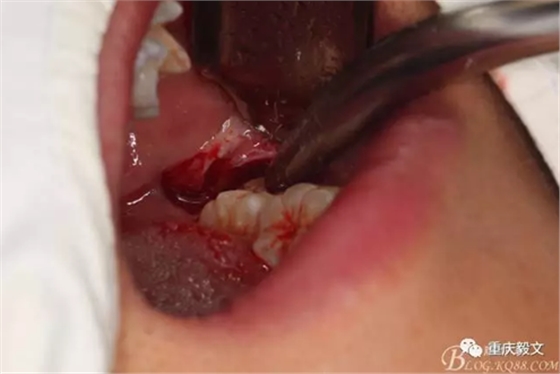

圖3 行左側(cè)下頜無(wú)痛下牙槽神經(jīng)阻滯麻醉:麻醉要點(diǎn):在大張口時(shí),上下頜牙槽突相距的中點(diǎn)線(xiàn)上與翼下頜皺襞外側(cè)3-4mm的交點(diǎn),作為注射標(biāo)志,將注射器放在對(duì)側(cè)口角,即第一、二前磨牙之間與中線(xiàn)成45°。注射針應(yīng)高于下頜牙 面1cm并與之平行。推進(jìn)2.5cm左右可達(dá)下頜骨骨面的下頜神經(jīng)溝?;爻闊o(wú)血,注入麻醉藥1-1.5ml。然后邊退針邊注射到粘膜下。這樣下牙槽神經(jīng)、舌神經(jīng)、頰神經(jīng)都麻醉。

圖4做角形瓣切口:切口注意事項(xiàng):遠(yuǎn)中切口勿過(guò)分偏向舌側(cè),側(cè)切口不超過(guò)前庭溝底,切開(kāi)時(shí)要切透全層,從遠(yuǎn)中切口前端,向后向頰側(cè)將瓣掀開(kāi)。頰側(cè)瓣掀至外斜線(xiàn)。